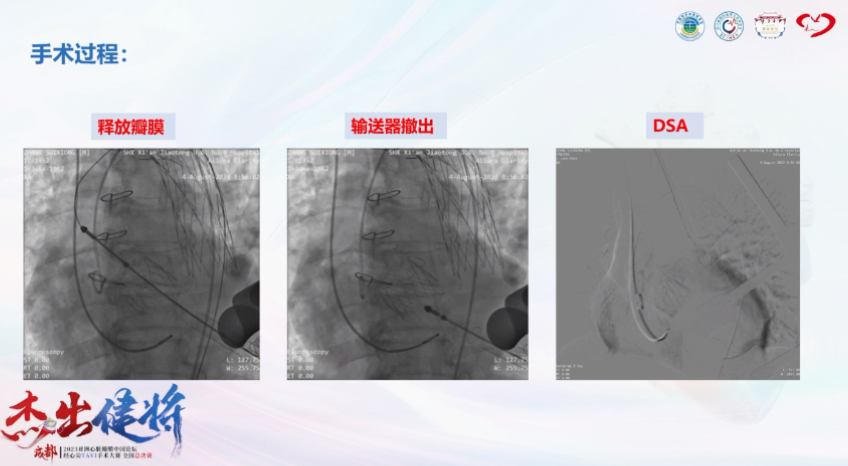

手术过程

术后复查心脏超声:主动脉流速1m/s,压差4mmHg,未见明显瓣周漏,EF 52%。